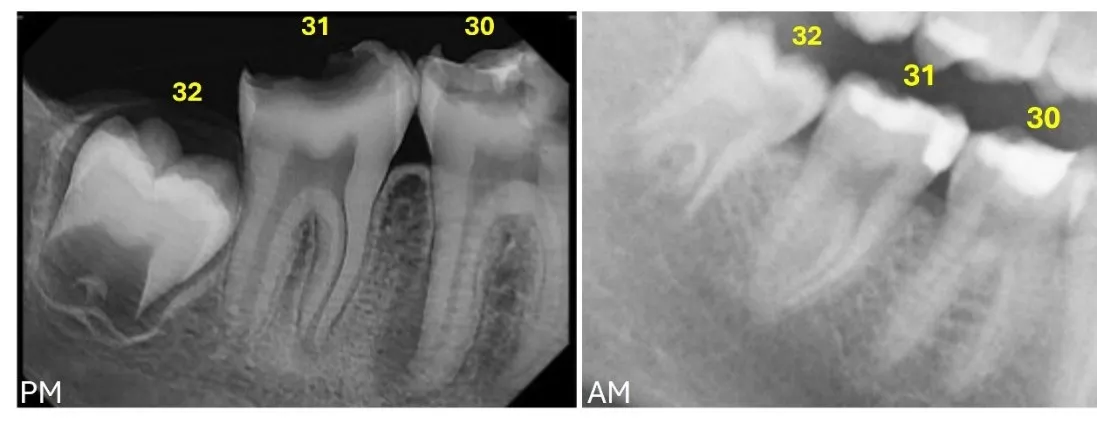

As previously mentioned in this article, the postmortem vs. the antemortem data comparison implies the evaluation of the consistencies and inconsistencies found in the data sets. This comparison is highly affected by the quality and completeness of the antemortem records, as well as the condition of the remains. The postmortem and antemortem odontograms and radiographs should be compared tooth-by-tooth [7], evaluating all the similarities and inconsistencies, and assessing whether these inconsistencies are reconcilable or irreconcilable. The principles of postmortem vs. antemortem odontological comparison are based on the differences in the dental and maxillofacial structures due to human variation, development and pathology, and the alteration caused by dental treatment, which can be visually and radiographically observed [6,7,12]. As such, the individual’s dentition changes throughout life. However, the changes are unidirectional [13], meaning that there are no reversals; this progressive change is fundamental to consider forensic odontology a reliable means of human identification. A match consists of several concordances between the postmortem and antemortem records. A restoration present in both data sets located in the same tooth, covering the same surfaces, and of the same restorative material represents a match (Figure 1). A reconcilable inconsistency consists of a discrepancy between the postmortem and antemortem records that may be explained by dental development or postformation changes, orodental disease and dental loss, new dental treatment or extension of a preexisting one, and skeletal trauma or surgery (Figure 2). Essentially, a reconcilable inconsistency will include all changes in the dentition that are plausible to have happened between the date in which the antemortem radiograph (or other record) was taken and the date in which the remains were found [5,6,8]. Reconcilable inconsistencies do not exclude the postmortem and antemortem records from corresponding to the same individual. An irreconcilable inconsistency includes any discrepancy between the postmortem and antemortem records that is not possible to occur (Figure 3). Tooth development and postformation changes are unidirectional, so the postmortem data cannot show an earlier stage of development for the same individual; a tooth presenting caries or a restoration cannot appear as healthy and not restored in the postmortem. Only one irreconcilable discrepancy is enough to exclude the antemortem and postmortem datasets from corresponding to the same individual.

Figure 3. Postmortem radiograph (PM) where #32 shows the initial formation of the bifurcation presenting a semilunar shape, whereas the antemortem (AM) radiograph shows #32 in a more advanced developmental stage, with a more extensive root bifurcation, the longer roots with divergent distal root canals (irreconcilable inconsistency) (Universal Dental Numbering System).